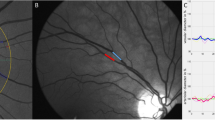

In a longitudinal design, 171 healthy Flemish children (53.8% boys) were followed-up for 7 years (2008–2015), aged 2.7–8.1 years at baseline.Z-scores of body mass index (zBMI; 4.1% overweight), waist circumference (zWC) and fat mass index (zFMI by BODPOD) were obtained using standardized protocols during each visit. Retinal arteriolar (central retinal arteriolar equivalent (CRAE)) and venular equivalents (central retinal venular equivalent (CRVE)) were measured from digital retinal photographs (2015) using IVAN software. Cross-sectional and longitudinal associations between changes in body fat and retinal microvasculature were explored using multivariable regression analysis, while controlling for age, sex, mean arterial pressure, alternate retinal caliber, physical activity, diet and birth weight.

In cross-sectional analysis, children with high zFMI had a higher CRVE, but only in boys (β=0.25, P=0.02). In addition, boys with high zFMI had also a lower CRAE to CRVE ratio (β=−0.26, P=0.03). No associations were seen with the CRAE, or between zBMI or zWC and the retinal microvasculature. Only changes in zFMI over time were found to be positively associated with the CRVE in boys (β=0.38, P=0.01).